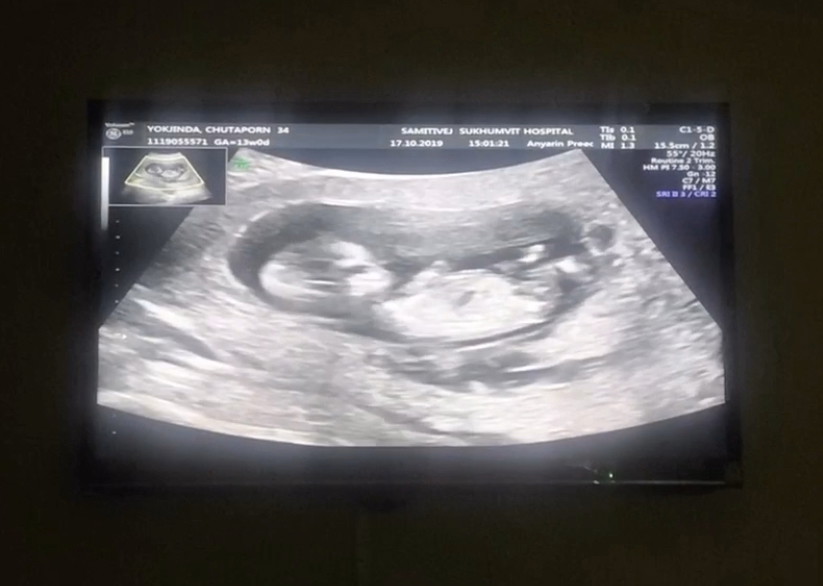

12week

Post reply image